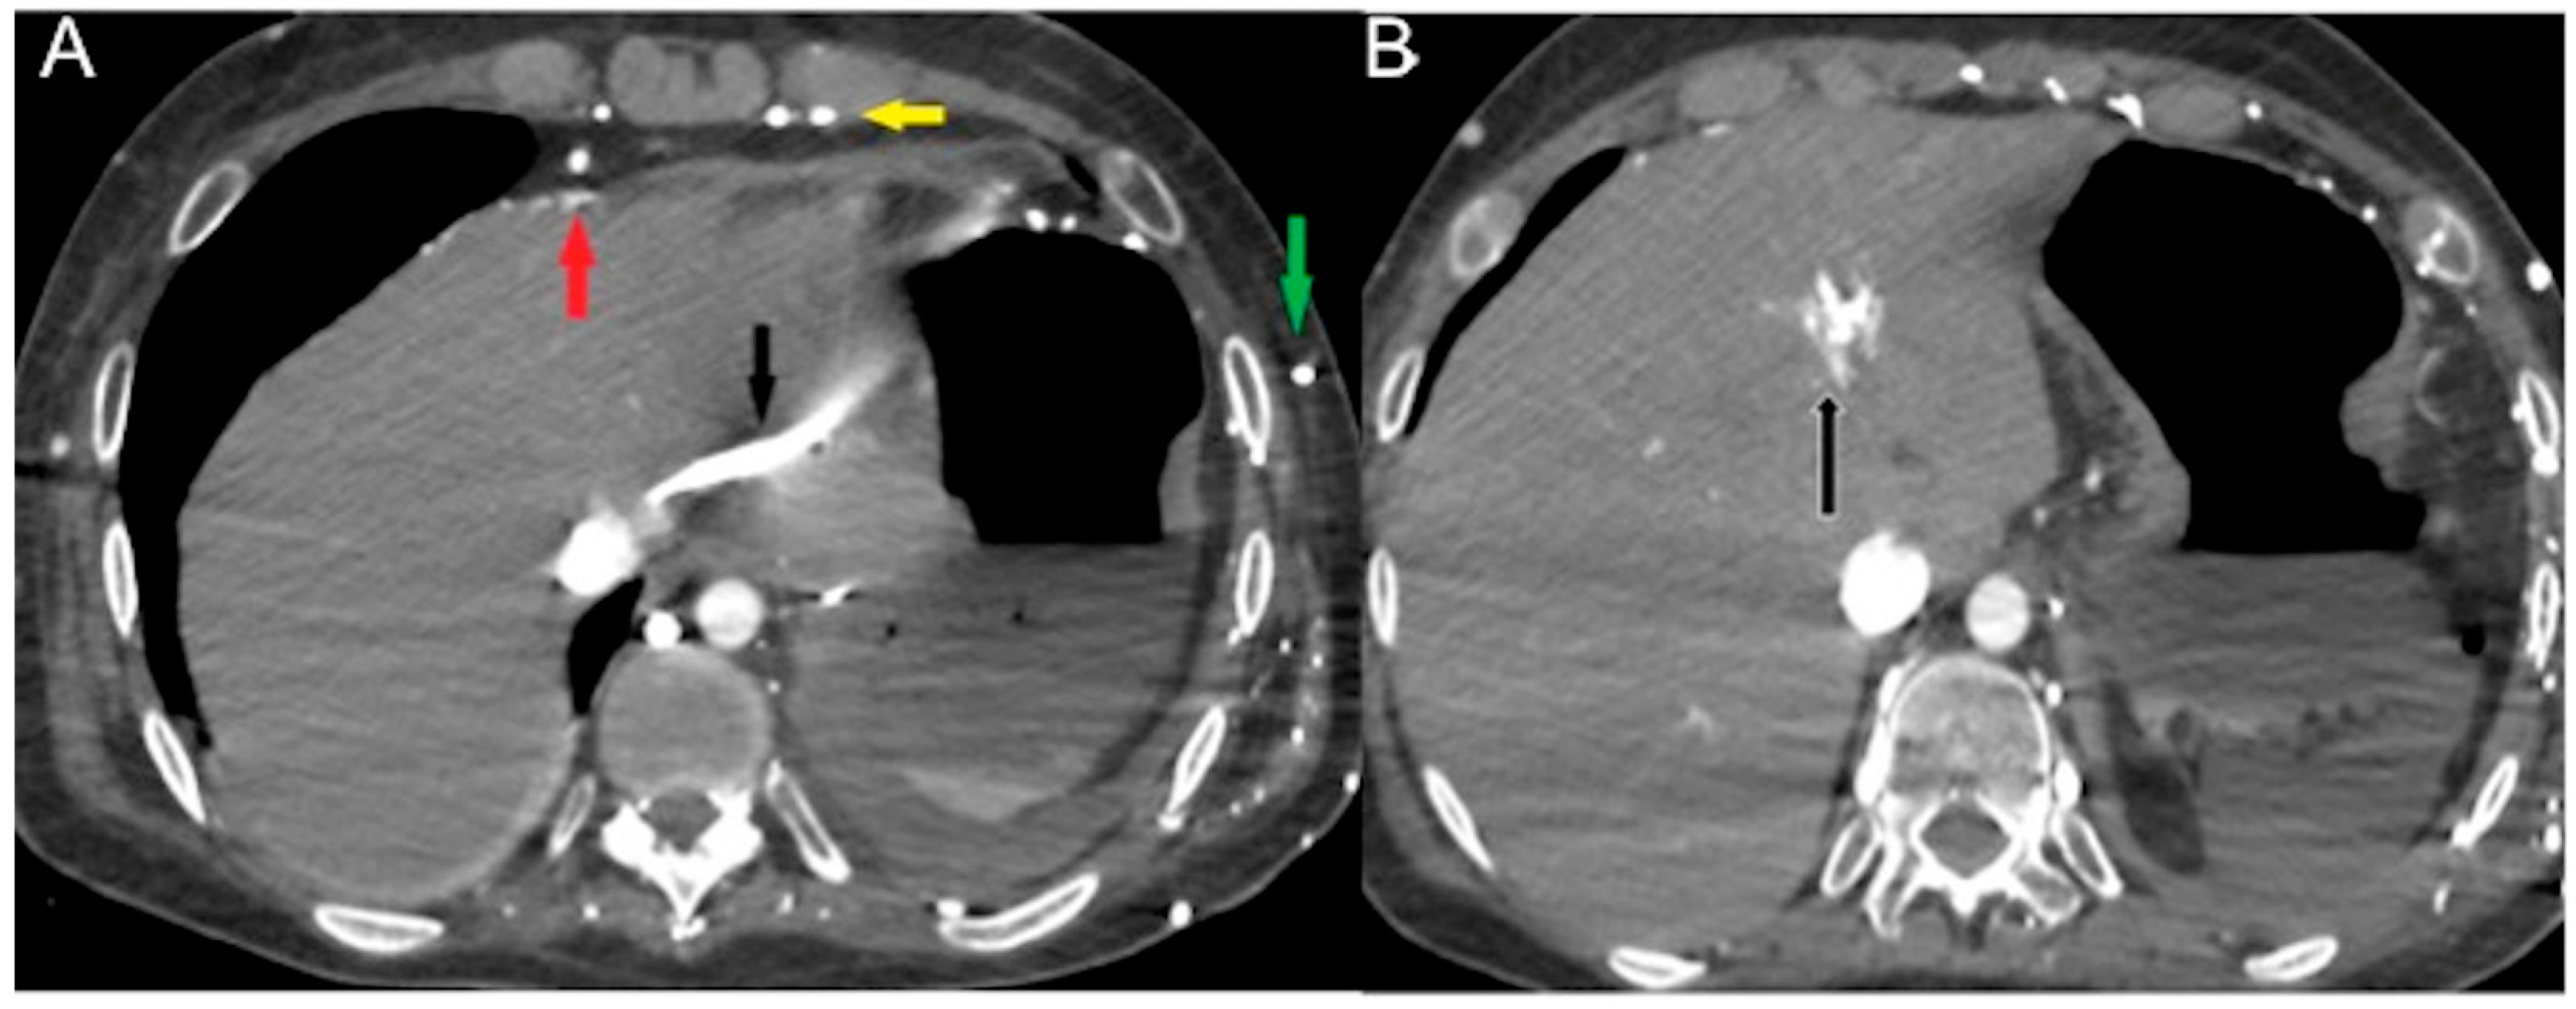

- In a state of advanced hemodynamic instability, many homeostatic mechanisms try to maintain arterial pressure and adequate tissue perfusion to critical organs, such as the brain and heart, by reflex stimulation of the sympathetic nervous system, elevated levels of angiotensin II, adrenaline, and noradrenaline, and vasoconstriction (compensated shock). Carotid baroreceptors respond to decreased blood pressure by triggering increased sympathetic signaling and maintaining cardiac output (sympathetic “fight or flight” response). In cases of decompensated shock, when compensatory mechanisms falter and prior to the onset of death, the pumping action of the heart ceases, leading to a substantial decline in systemic arterial and venous pressures. Consequently, the arteriovenous pressure gradient diminishes [6,41,42]. This altered hemodynamic state results in stasis of CM in the venous system in the presence of the left chamber and arterial opacification, and of other infrequent and often unappreciated ominous MDCT vascular signs that represent a true hypovolemic state and must be recognized early by the radiological staff to improve survival [24,43,44,45,46,47,48]. This may be called the “venous CM pooling and layering” pattern, indicating that compensatory mechanisms are becoming insufficient and the patient must receive immediate treatment.

- In irreversible end-organ dysfunction, injected IV CM circulation is supported only by the pressure applied by the automated power injector and the density of contrast material. Circulatory arrest leads to dense contrast pooling and layering in the SVC, IVC (inferior vena cava), and right heart chambers with non-opacified left heart chambers or arterial vessels (Figure 1) [43,45,49,50,51,52]. This may be called the “non-beating heart” pattern. Cardio-pulmonary aggressive resuscitation must immediately be initiated within the framework of a predetermined emergency plan.

- There is the presence of a slit-like or flat inferior vena cava (FIVC) (Figure 2A). This is characterized by an anterior-posterior diameter of less than 9 mm in three consecutive segments, 20 mm above and below the renal veins, and at the level of the perihepatic region. Additionally, a transverse-to-anteroposterior ratio of ≥2.5 at the level of the suprarenal IVC can indicate flattening. The flatness index or IVC diameter ratio is calculated by dividing the maximal transverse and anteroposterior diameters of the IVC [15,16,17,18,19,20,21,22,23,24,25,26,27,28,29,30,31,32,57,58,59,60,61].

- The IVC halo sign is characterized by a low attenuation band (<20 HU) encircling the collapsed intra- and retrohepatic inferior vena cava. This band is caused by a ring or rim of edema [65,66,67]. In cases of severe hypovolemia, approximately 80% of patients may exhibit this sign, resulting from the loss of precapillary arteriolar sphincter tone and the accumulation of fluid surrounding the IVC (Figure 2B–D) [18,25,30,31,65,66,67]. However, it is important to note that this sign is not specific to non-traumatic patients and can also be observed in conditions such as liver congestion, biliary cirrhosis, hepatitis, or other diseases that obstruct lymphatic drainage at the porta hepatis [25].